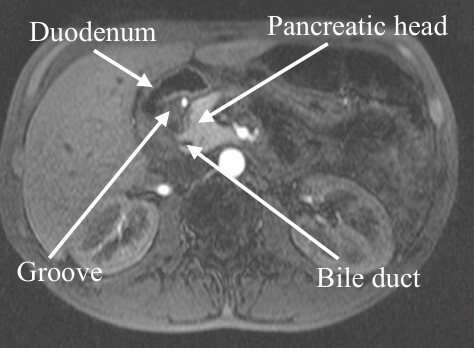

Background: Groove pancreatitis (GP) is a rare, segmental form of chronic pancreatitis that primarily affects individuals between 40 and 50 years of age. It has been referred to by various other names, such as paraduodenal pancreatitis, cystic dystrophy of heterotopic pancreas, duodenal dystrophy, duodenal pancreatic hamartoma, paraduodenal wall cyst, and myoadenomatosis. This distinct and sporadic form of pancreatitis (GP) can be classified, depending on the affected segment, into a segmental form - affecting the entire pancreatic head - and a pure form limited to the pancreaticoduodenal groove, with preservation of the remaining pancreatic parenchyma. Its true incidence, as well as its pathophysiological mechanisms, remains unknown.

Background: Groove pancreatitis (GP) is a rare and segmental form of chronic pancreatitis that affects the pancreaticoduodenal sulcus. Its pathophysiology is still not well known, and several etiological factors have been attributed, with chronic alcohol consumption being the most common association. Its treatment still generates controversy. The initial clinical approach followed by endoscopic therapies prevails. Surgery is indicated when these treatment options fail.

Results: A total of eight patients were included, of whom six were male, and their mean age was 45 years. The main symptom presented was long-standing abdominal pain with the use of analgesics and weight loss; all patients were chronic alcoholics. Imaging methods defined the diagnosis of GP in the preoperative period in five patients. In three patients, the preoperative diagnosis was neoplasia of the head of the pancreas. All patients underwent pancreaticoduodenectomy and one patient developed pancreatic fistula. There was a regression of pain in all patients.